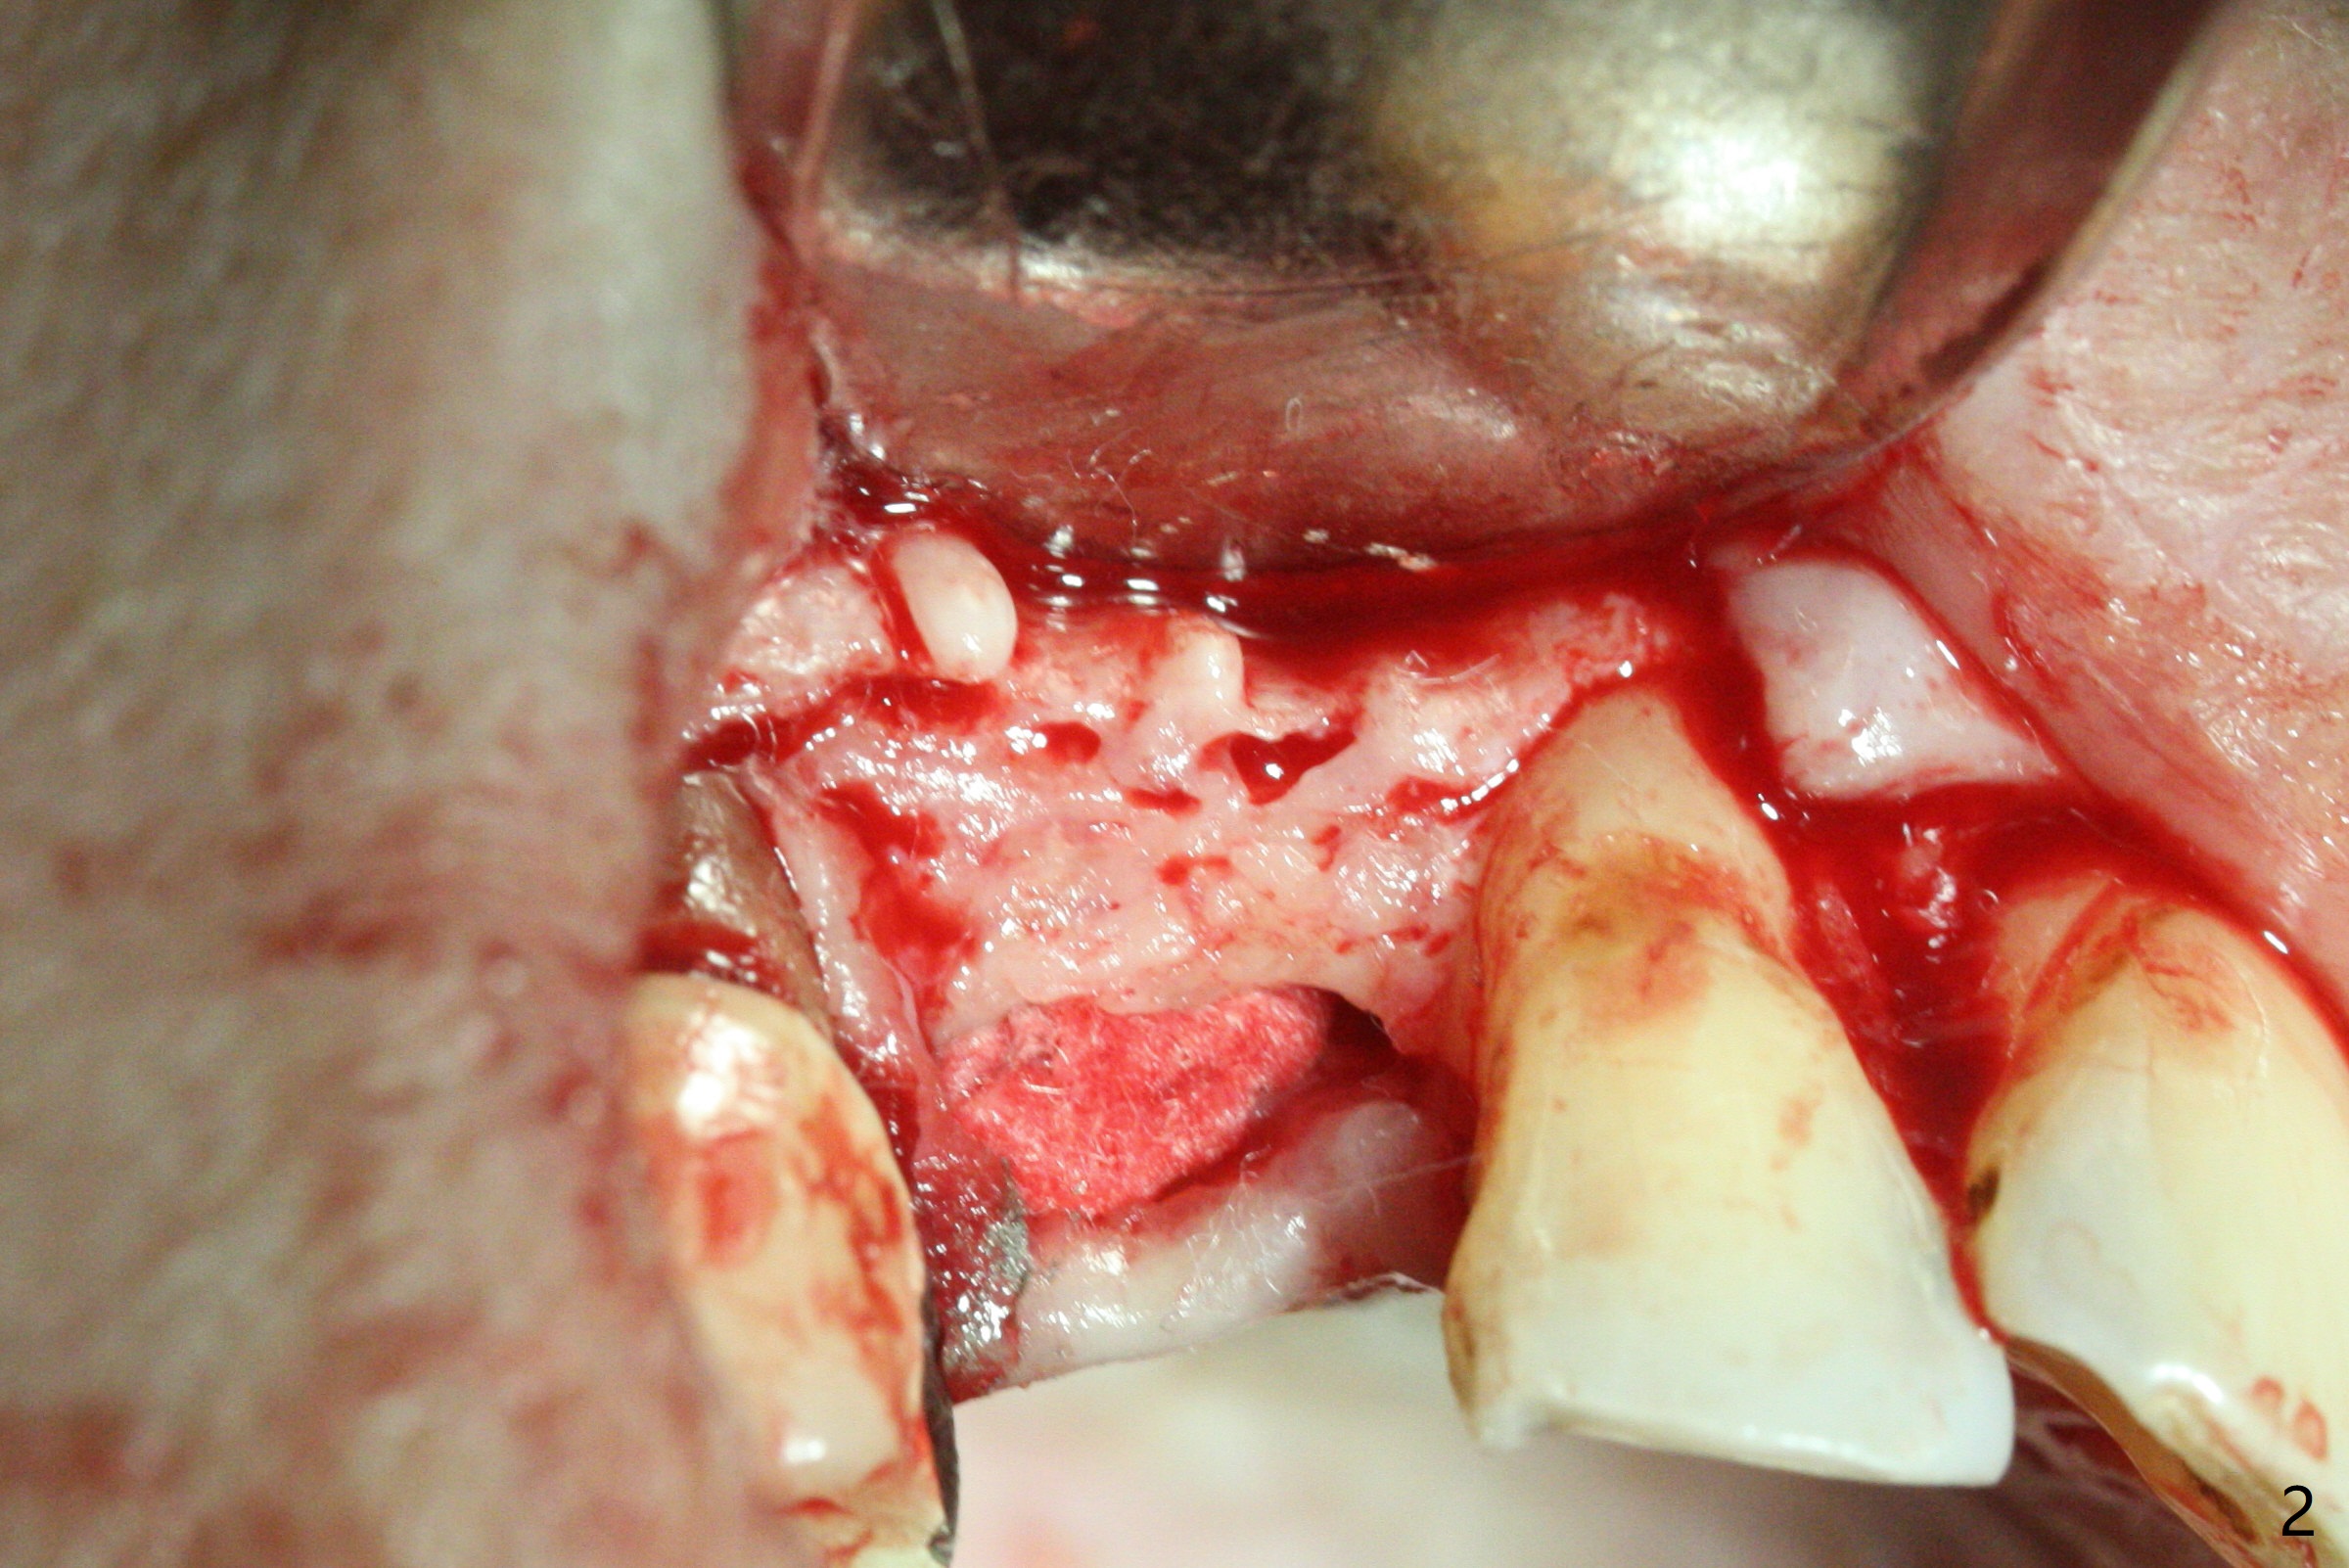

After removal the pontic of a cantilever FPD (Fig.1), a residual root is found at #6 with the buccal concavity (Fig.2 *). The ridge is narrow with flap elevation (Fig.3). PA taken with a 1.2 mm drill for 14 mm shows a horizontally impacted canine (Fig.4: #6). When the osteotomy is finished without apparently buccal perforation (Fig.5), the trajectory is buccal. When a 3x14 mm (12.5 mm in bone) 15 degree angled 1-piece implant is placed with normal trajectory (Fig.6), the buccal plate is perforated. As the implant is redirected so that the apical end of the implant does not stick out buccally, the trajectory returns buccal (Fig.7). The buccal aspect of the abutment is heavily reduced for an immediate provisional. The perforation is repaired with Vanilla Graft and Collagen Dressing before suturing. CT should have been taken preoperatively; the osteotomy should have been initiated as palatal as possible, as compared to that in Fig.5. When the 1st drill is used. it should be checked for restoration. An angled abutment does not help the trajectory substantially. The implant is loose 1.5 months (partially due to mastication); after retightening, CT is taken (Fig.8). The implant is within the bone. If the implant becomes loose again, extract the impacted canine and place the longest implant (22 mm) palatally. The implant is stable nearly 4.5 months postop (Fig.9). The patient is not satisfied with buccally-placed crown. The implant is removed with bone graft 6 months postop.